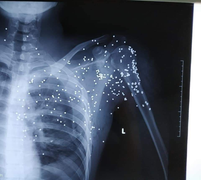

Lúc này, Đại mở cửa xe, nổ súng hoa cải khiến B.H.H hứng trọn loạt đạn dẫn đến trọng thương. Sau khi gây án, Bùi Xuân Đại bỏ trốn. B.H.H được đưa đi cấp cứu tại Bệnh viện Đa khoa tỉnh Thái Bình, sau đó được chuyển lên Bệnh viện Hữu nghị Việt Đức (Hà Nội) để tiếp tục cấp cứu và điều trị.